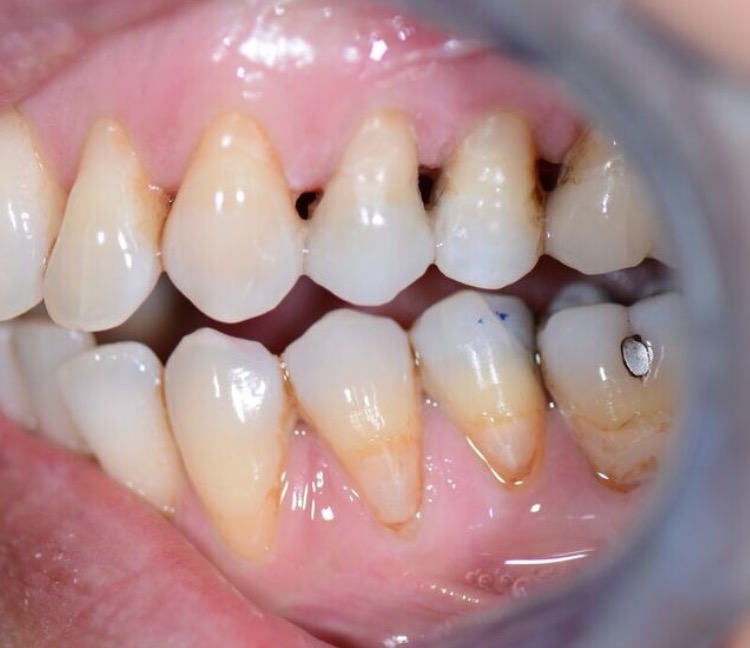

Nos réalisations : Conjointe

Céramique sur Zircone

Biocompatible elle est garante d’une excellente intégration gingivale.